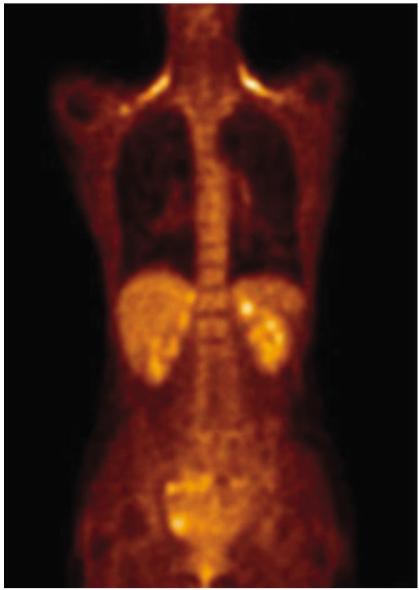

Fluorodeoxyglucose (FDG)-positron emission tomography (PET) is being used more and more to differentiate benign from malignant focal lesions and it has been shown to be more efficacious than conventional chest computed tomography (CT). However, FDG is not a cancer-specific agent, and false positive findings in benign diseases have been reported. Infectious diseases (mycobacterial, fungal, bacterial infection), sarcoidosis, radiation pneumonitis and post-operative surgical conditions have shown intense uptake on PET scan. On the other hand, tumors with low glycolytic activity such as adenomas, bronchioloalveolar carcinomas, carcinoid tumors, low grade lymphomas and small sized tumors have revealed false negative findings on PET scan. Furthermore, in diseases located near the physiologic uptake sites (heart, bladder, kidney, and liver), FDG-PET should be complemented with other imaging modalities to confirm results and to minimize false negative findings. Familiarity with these false positive and negative findings will help radiologists interpret PET scans more accurately and also will help to determine the significance of the findings. In this review, we illustrate false positive and negative findings of PET scan in a variety of diseases.